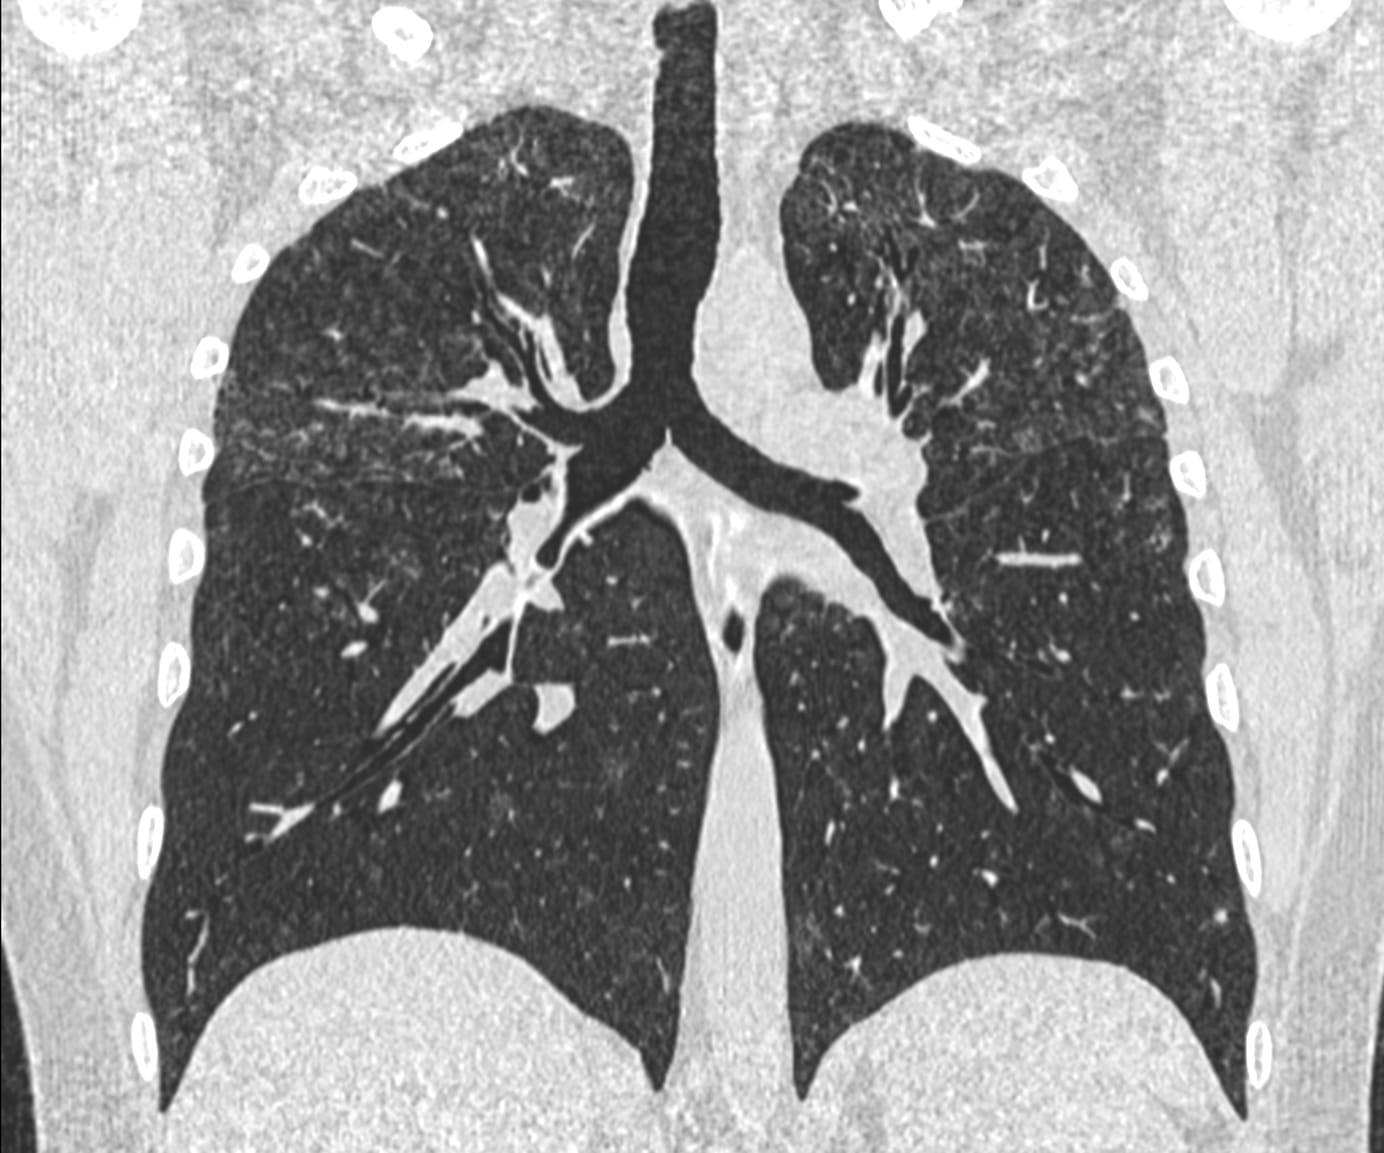

41-years old was diagnosed to have Stage III sarcoidosis last year (peribronchovascular and fissures nodules - panels C and D). He was put on treatment and the scan done recently shows significant improvement (panels A and B).

It is the pattern of improvement that is interesting. While the extent of disease is more or less unchanged, it is the density of the lesions that has regressed. The dense discrete nodules have given way to subtle ground glass with reticular opacities resembling cotton candy or melted sugar or a faint tint.